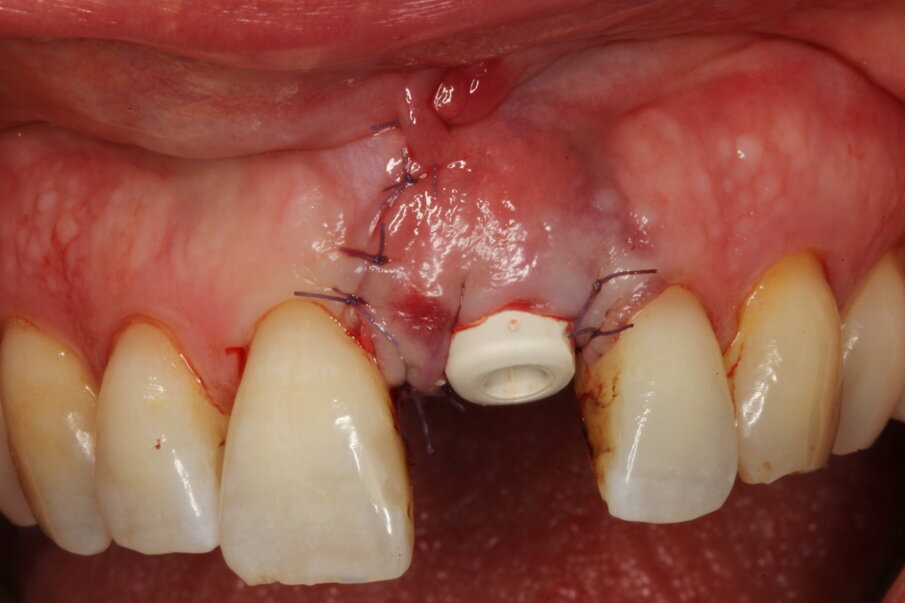

Local anaesthesia was performed with 2% mepivacaine with 1:100,000 adrenaline. Preventative antibiotic therapy with amoxicillin (1 g, b.d. for five days) was prescribed, aided by use of a 0.2 % chlorhexidine mouthrinse three times a day for one minute. The tooth was extracted and the sulcular epithelium removed with diamond burs. The milled surgical template (Figs. 12 & 13) served as a guide for the first 2 mm diameter pilot drill (Fig. 14). Thus, the planned depth, position and angulation of the osteotomy were obtained. The drill sequence was completed freehand, using tapered 3.0 and 3.4 mm drills. A Neoss Pro- Active Tapered Implant of 4 mm in diameter and 13 mm in length was inserted flush with the mesial/palatal/distal bone, motor driven up to a torque of 50 Ncm and then with a manual wrench (Fig. 15). The correct position of the internal hex was verified by checking the references on the implant driver, which ideally points in the buccal direction. Resonance frequency analysis with Penguin RFA (Integration Diagnostics Sweden) determined an ISQ value of 73/76. At this stage, a Neoss Esthetic Healing Abutment with a ScanPeg was connected to the implant (Fig. 16). A flap was then raised after a vertical incision of the frenulum and the expected buccal exposure of the implant neck was evident. Autogenous bone harvested from the drills was positioned directly on the implant surface (Fig. 17), followed by a bone substitute on top of it and on the buccal cortical bone (Fig. 18). This material was covered with a resorbable membrane (Fig. 19). The mobilised flap was then repositioned by rotating it coronally and fixed with single sutures (Fig. 20). The removable partial denture was adapted and delivered (Fig. 21). An immediate postoperative CBCT scan of 60 x 60 mm was performed, and it confirmed a perfectly centred implant position (Figs. 22 & 23).

Eight days after surgery, the patient reported that healing was uneventful and the prosthodontist removed the stitches. It has become the author’s standard protocol to perform an intraoral scan for implant position in this same session (Figs. 24 & 25). The specific and unique PEEK healing abutment used has an internal circular channel and on one side, normally positioned on the buccal aspect, a vertical rectangular slot (Fig. 26). After removing the PTFE tape used to plug this area during surgery, a ScanPeg can be positioned inside the healing abutment. This allows for a unique scanning procedure without removing the healing abutment, thus avoiding disturbing healing tissue or dislocating recently placed biomaterials. The producer provides libraries for STL files of the five different anatomical shapes—wide incisor, narrow incisor, canine, premolar and molar—that determine the basic profile of the gingival tunnel during healing.